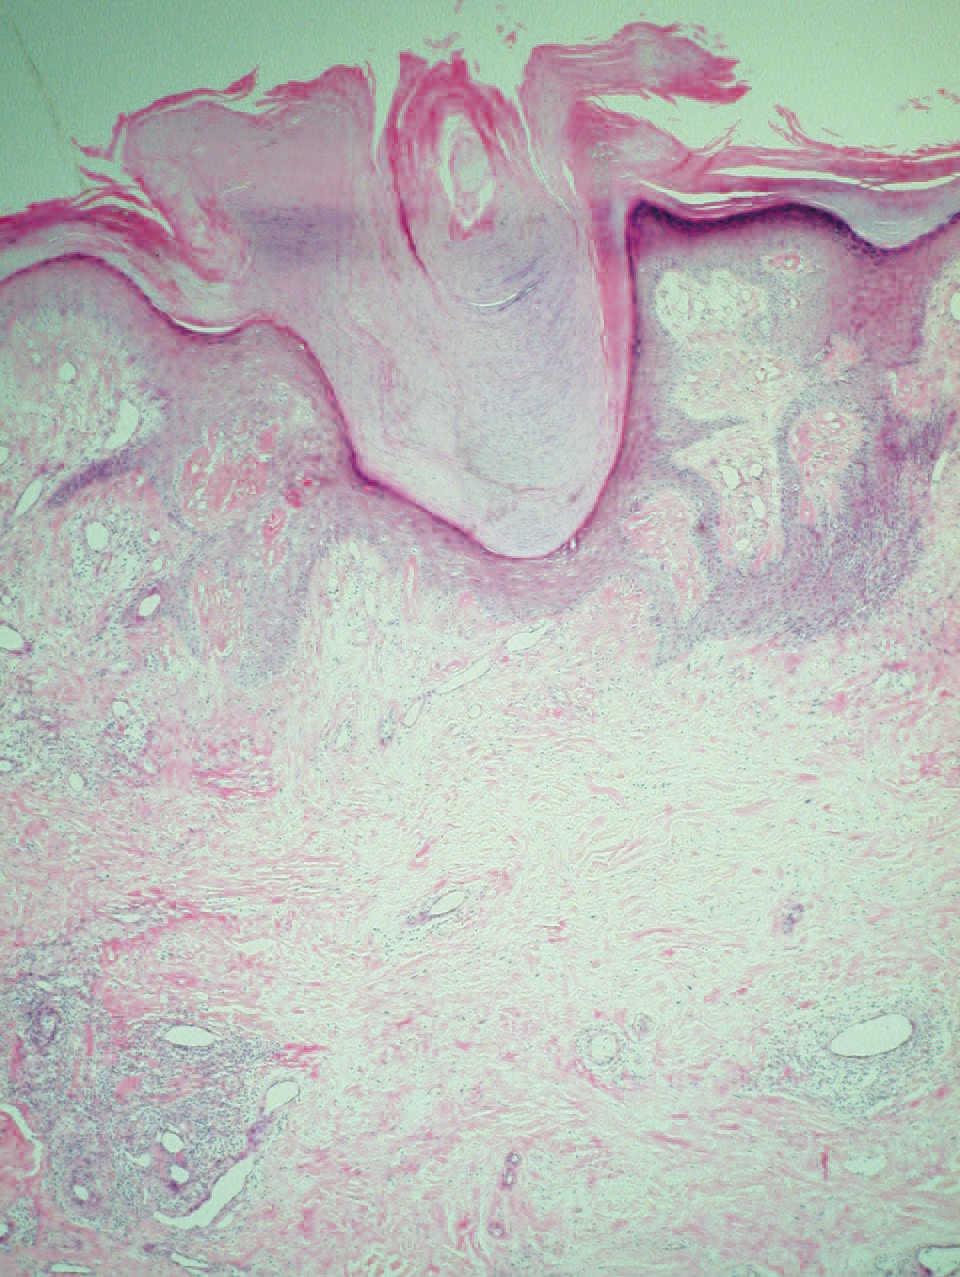

El examen histopatológico de la biopsia cutánea mostró columnas paraqueratósicas bien definidas con límites precisos con la epidermis ortoqueratósica normal adyacente, algunas de las cuales emergían de una capa granulosa moderadamente disminuida (fig. 2). La dermis superior mostraba un ligero infiltrado inflamatorio y algunos capilares dilatados. No se detectó vacuolización de queratinocitos ni disqueratosis.

Figura 2. Columna paraqueratósica que asienta sobre una capa granular adelgazada. (Hematoxilina-eosina, 40.)

El principal hallazgo histológico de la HF paraqueratósica es una columna de células paraqueratósicas bien definida que recuerda a la lamela cornoide de las poroqueratosis. Para evitar confusión, Lestrigant y Berge8 acuñaron el término «paraqueratosis columnar» en referencia a este hallazgo. La columna paraqueratósica asienta generalmente sobre una capa granulosa reducida o incluso ausente y un estrato de Malpighio ligeramente adelgazado. Presenta límites muy bien definidos con respecto a la epidermis normal adyacente y ocasionalmente puede verse en relación con folículos pilosos5,16 y con el acrosiringio6,17,19, de forma similar al nevus ductal poroqueratótico ecrino21. Mehta et al13 describieron un caso que mostraba la coexistencia de columnas orto y paraqueratósicas. Raramente puede observarse vacuolización de queratinocitos22. En estos casos resulta más complicado rechazar firmemente la hipótesis que sugiere algún tipo de asociación entre esta entidad y la poroqueratosis, pero contrariamente a lo que sucede en ésta, en la HF paraqueratósica no se observa disqueratosis ni angulación en la columna. La dermis subyacente no muestra alteraciones significativas en la mayoría de los casos, sin embargo, en ocasiones puede observarse un ligero infiltrado inflamatorio15 y dilatación de capilares5,6.